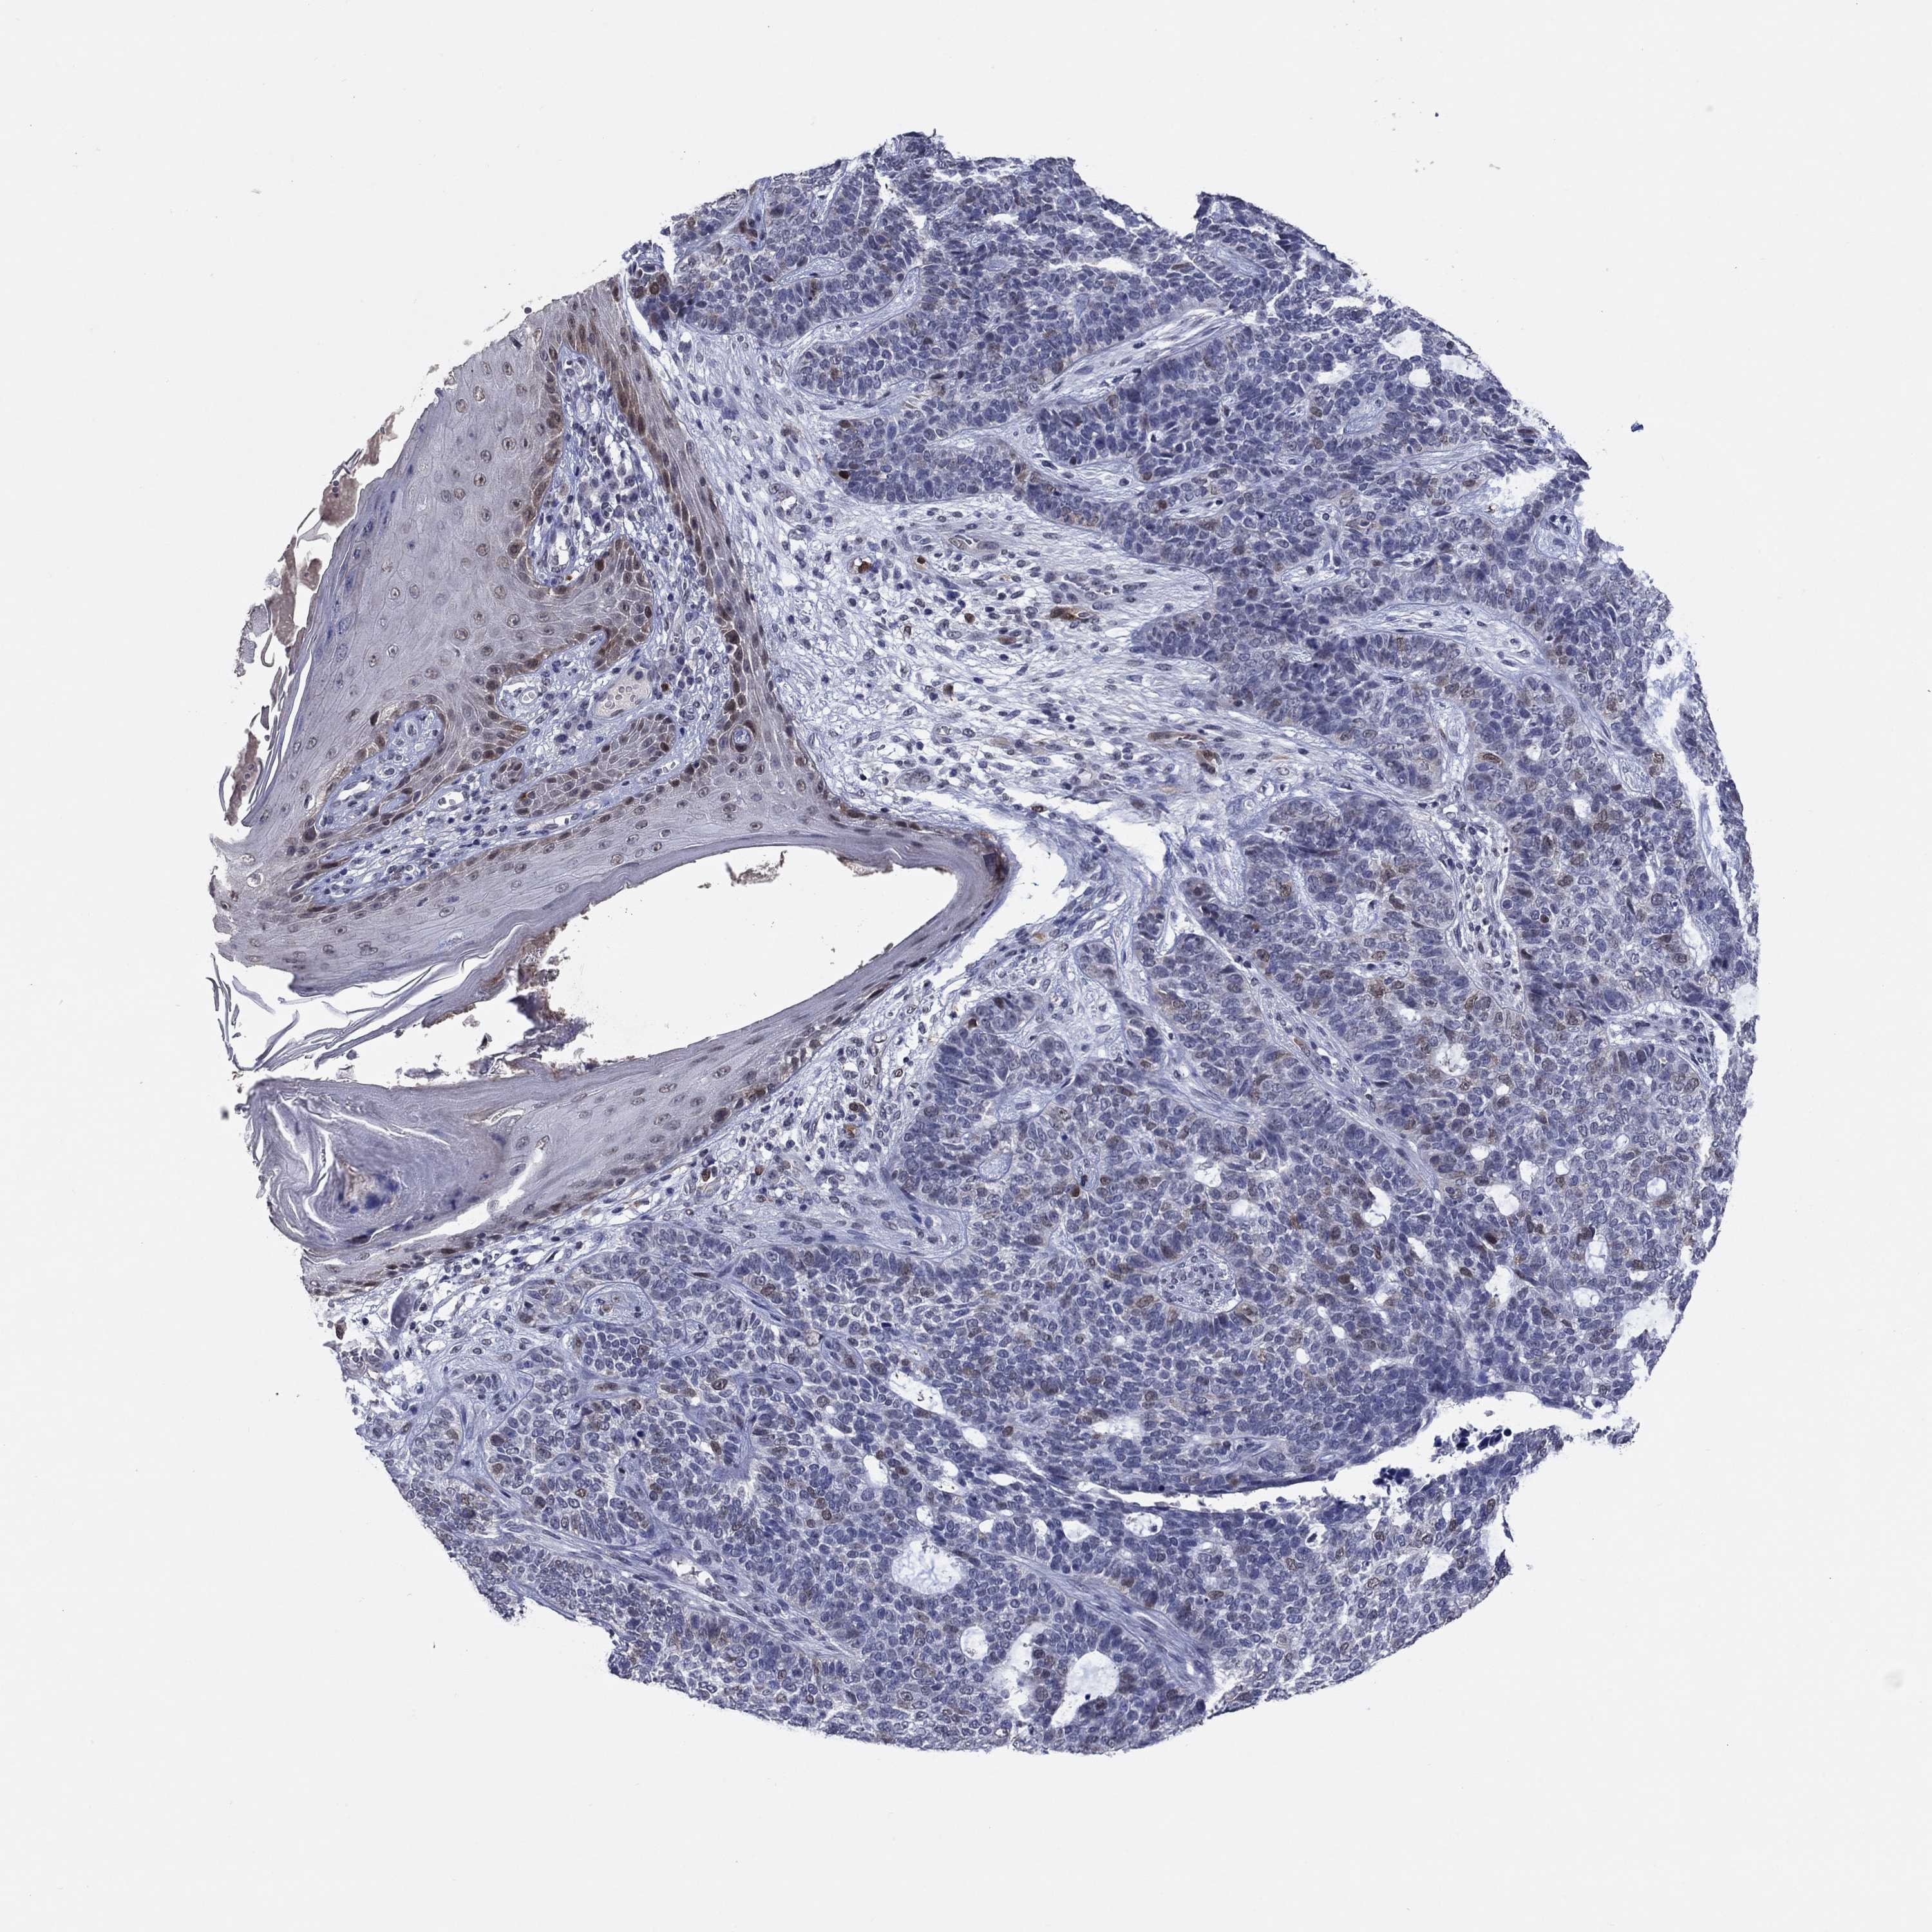

SKIN CANCER - Protein expressioni

A mouse-over function shows sample information and annotation data. Click on an image to view it in a full screen mode. Samples can be filtered based on level of antibody staining by selecting one or several of the following categories: high, medium, low and not detected. The assay and annotation is described here.

Antibody staining in the annotated cell types in the current human tissue is reported as not detected, low, medium, or high, based on conventional immunohistochemistry profiling in selected tissues. This score is based on the combination of the staining intensity and fraction of stained cells.

Each image is clickable and will lead to virtual microscopy that enables deeper exploration of all samples and also displays staining intensity scores, fraction scores and subcellular localization as well as patient and tissue information for each sample.

Antibody HPA074922

Antibody CAB002784

Staining

High

Medium

Low

Not detected

Intensity

Strong

Moderate

Weak

Negative

Quantity

>75%

75%-25%

<25%

None

Location

Nuclear

Cytoplasmic/membranous

Cytoplasmic/membranous,nuclear

Basal cell carcinoma

Squamous cell carcinoma, NOS